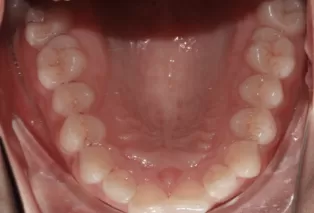

Intraoral photos

Intraoral photos after treatment